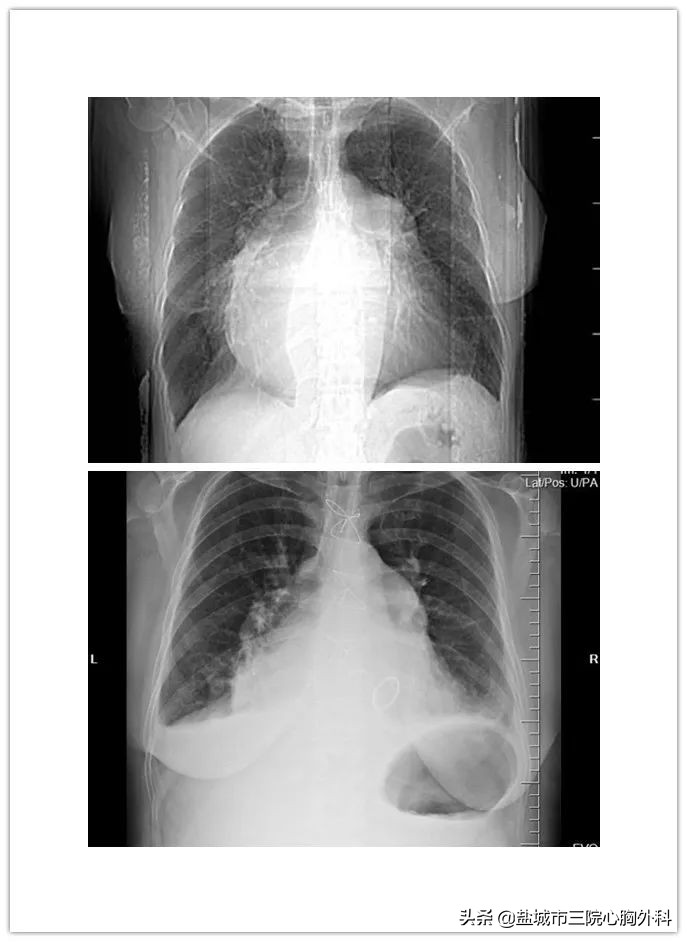

心胸外科副主任医师施展表示,刘阿姨目前心脏明显扩大,大小超过正常人的三倍,几乎达到了牛心脏的大小,胸腔都快被心脏填满了,这是病情恶化的重要表现,目前手术势在必行,再加上患者有过开胸手术史,心包容易存在致密粘连,无疑增加了手术难度。

(上图为术前胸片,下图为术后胸片,心脏已基本恢复正常大小)